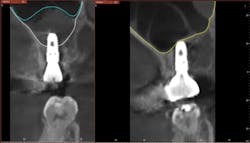

Hydraulic sinus lifting is a technological leap forward in sinus lift procedures. These innovative devices utilize hydraulic pressure to lift the sinus membrane gently and precisely, creating sufficient space for implant placement without the need for excessive bone manipulation (figure 3).

Hydraulic lifts can effectively prevent many of the aforementioned complications. Membrane perforations and injury to nearby vital structures are minimized because of the use of millimeter-precise drill stoppers, as well as simply using saline instead of blunt instruments to separate the thin sinus membrane. The flat-ended drills and stoppers in hydraulic techniques eliminate much of the guesswork involved in drilling to breach the sinus.

There is no manual bone manipulation, meaning hydraulics are less invasive and therefore promote faster healing for patients. Because mallets are not used, the patient experiences less trauma and doesn’t suffer related side effects such as tinnitus or concussions. Most importantly, unlike traditional methods that involve manual force, hydraulic lifts offer controlled and predictable elevation of the sinus floor, minimizing trauma to surrounding tissues and reducing postoperative complications.

As the landscape of implantology evolves, the adoption of hydraulic lifts is poised to become the gold standard in noninvasive sinus lift surgeries, reshaping the future of dental implant procedures (figures 4–11).